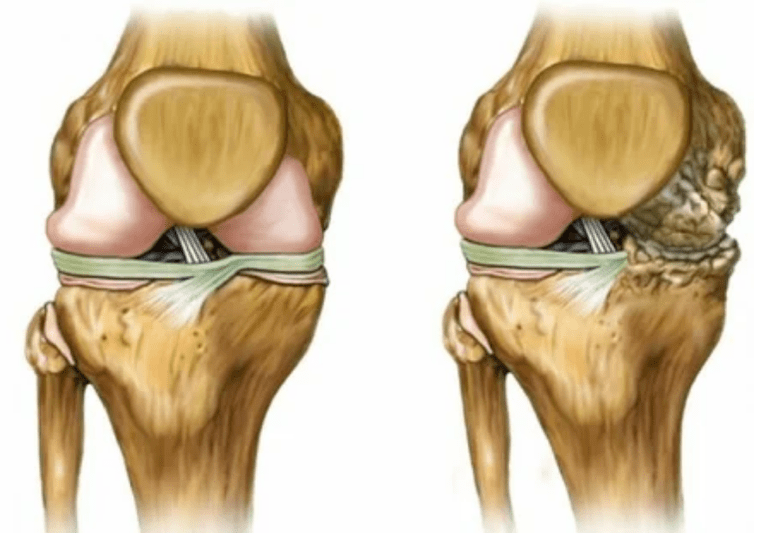

- Reduce gaps in joint gaps, which become apparent in the picture.The stage of violation is determined by a diagnostic terminologist.The patient feels complex or is unable to completely straighten and bend the limb.

- The joints are deformed, and the cartilage obtains irregular shapes, causing curvature;

- The patient's condition worsens due to complete damage to the joints.

- Stage 2.Due to insufficient supply, the necessary cartridges are damaged, forming bone growth on the surface of the cartilage.Pain gains a more obvious feature, exacerbates after a long period of rest, and is eliminated by small-scale physical labor.Pain accompanied by inflammation.The muscles are stretched, resulting in weaker motor function or average impairment.

- 3 degrees.Usually there is pain, and it is difficult to move the limbs due to changes in joints.The lesions are widespread and the appearance of becoming naked is obvious.Deformation of the joint site occurs, and the affected area expands and turns red.The limb axis is disturbed, which leads to the complexity of the movement.Pathological changes can cause shortening of ligaments.Transitional and State parties emerged.The adjacent muscles are shortened or stretched, and the contraction function is weakened.